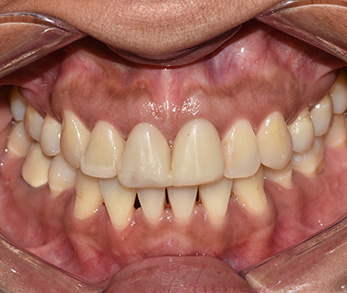

Teeth Whitening + Ceramic Crowns

Amity Harbor Dentistry | LANAP reg , Emergency Treatment and Implant Dentistry

Before

Amity Harbor Dentistry | Cosmetic Dentistry, Dental Cleanings and Root Canals

After